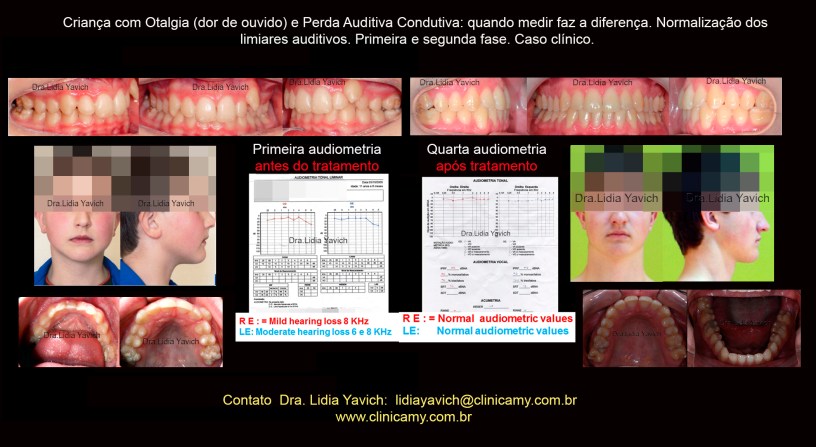

Imagens da oclusão habitual do paciente e vista oclusal superior e inferior. Fotografias do paciente sorrindo de frente e perfil no dia da consulta.

A primeira audiometria do paciente revela uma discreta hipoacusia no ouvido esquerdo e uma leve hipoacusia no ouvido direito.

A segunda audiometria do paciente revela limiares normais no ouvido esquerdo e uma discreta hipoacusia no ouvido direito.

Comparação da primeira e a segunda audiometria do paciente durante o tratamento.

Normalização dos limiares no ouvido direito e melhora nos limiares do ouvido esquerdo.

A terceira audiometria do paciente revela limiares normais no ouvido esquerdo e limiares normais no ouvido direito.

Comparação da primeira, segunda e terceira audiometria do paciente durante o tratamento.

Normalização dos limiares no ouvido direito e normalização dos limiares do ouvido esquerdo.

Imagens comparativas da vista oclusal superior e inferior do paciente antes e após a finalização da primeira e a segunda fase do tratamento neurofisiológico.

A quarta audiometria do paciente após a finalização das duas fases do tratamento mantém os limiares normais no ouvido esquerdo e limiares normais no ouvido direito.

Comparação da primeira, segunda, terceira e quarta audiometria do paciente.

Normalização dos limiares no ouvido esquerdo e no ouvido direito.